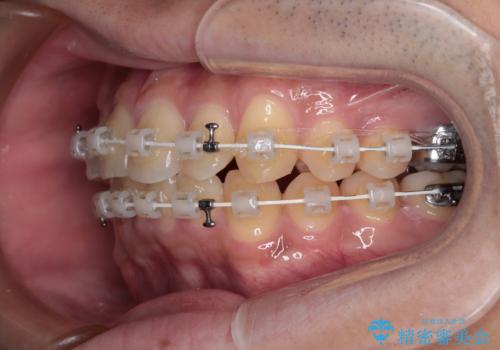

- 上下前歯の捻れやデコボコを気にして来院された患者様です。

マウスピース矯正でもワイヤー矯正でも対応可能でしたが、極力楽をして治したいとのことでワイヤー装置にて治療をおこなうこととしました。

口元はそれほど突出しておらず、患者様自身も気にしていらっしゃいませんでしたが、前歯の捻れやデコボコを解消すると、前方に拡大され、治療後に出っ歯仕上がりとなるリスクがあったため、補助装置により上顎臼歯を後方移動していくこととしました。

昼休みを活用して通院してくださり、1年半であっという間に終えることができました。